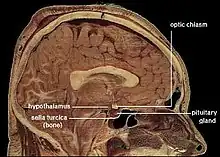

The corpus callosum forms the floor of the longitudinal fissure that separates the two cerebral hemispheres. Part of the corpus callosum forms the roof of the lateral ventricles.[5]

The callosal sulcus is a sulcus that separates the corpus callosum from the cingulate gyrus.

The anterior cerebral arteries are in contact with the undersurface of the rostrum; they arch over the front of the genu and are carried along the trunk, supplying the front four-fifths of the corpus callosum.[7]